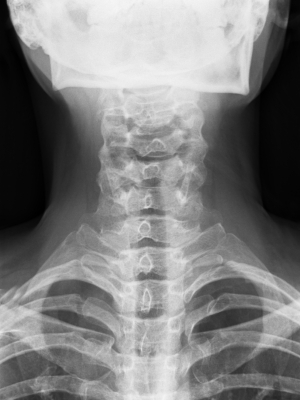

Видео рентгеноскопии является одним из видов рентгеноскопии, который использует видео для сбора и хранения изображений. Рентгеноскопия является сбор рентгеновских лучей, когда пациент совершает акт, такие как глотание. Изображения позволяет врачу наблюдать за функции организма в режиме реального времени движение. Он широко используется для изучения функции легких и диафрагмы, кости шеи и анализ глотания.